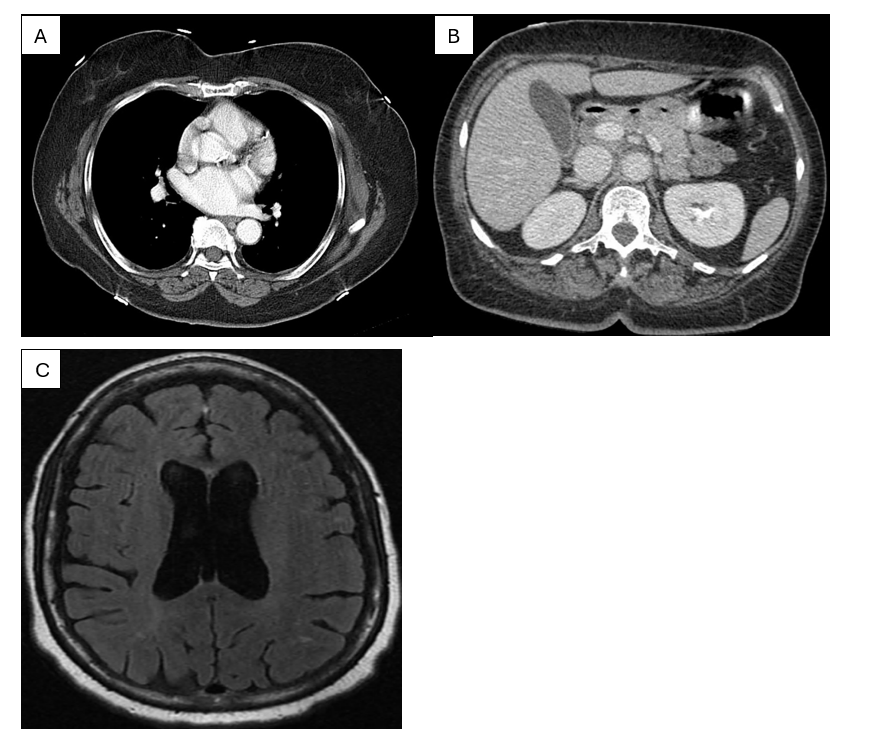

Figure 1 shows an occurrence between two sinus beats without a compensatory pause and a constant P-P interval. A chest x-ray was completed, showing no evidence of acute cardiopulmonary disease. A computed tomography (CT) angiogram of the chest was completed to rule out a pulmonary embolism. There was no evidence of pulmonary embolus, focal consolidation, pleural effusion, or pneumothorax. It was noted that she had three pulmonary nodules and that her thyroid was enlarged. An ultrasound of the abdomen was unremarkable, while the CT of the abdomen and pelvis showed minimal biliary dilation and moderate to severe atherosclerotic calcification of the abdominal aorta, but was otherwise unremarkable. A CT of the head without contrast was largely unremarkable for her age, showing no evidence of acute intracranial hemorrhage or definite infarction. There were nonspecific periventricular and subcortical white matter changes, which were likely to represent small-vessel ischemic disease, consistent with the patient’s age.

Magnetic resonance imaging (MRI) of the brain to further evaluate her ongoing dizziness showed no evidence of acute territorial infarction, intracranial hemorrhage, or mass. The mid bilateral periventricular and deep white matter showed chronic microvascular ischemic changes and generalized cerebral atrophy. An echocardiogram was ordered and revealed a normal left ventricular cavity size and mildly increased left ventricular wall thickness. Global systolic function was low-normal global left ventricular contractility. Left ventricular ejection fraction of 50-55%. The right ventricle was mildly dilated. Right ventricular systolic function was normal. The aortic valve is a tri-leaflet valve. There was mild aortic stenosis (peak velocity 2.6m/s, mean gradient 15 mmHg, Doppler velocity index (DVI) = 0.60). There was no aortic regurgitation. The mitral leaflets were mildly thickened and calcified. Severe mitral annular calcification was present (posterior > anterior). There was reduced mobility of the posterior leaflet. There was mitral stenosis that was likely attributed to restricted leaflet motion in the setting of severe mitral annular calcifications (MAC).

Figure 2: (A) CT pulmonary angiogram demonstrating normal opacification of the pulmonary arteries with no evidence of pulmonary embolism. (B) Contrast-enhanced abdominal CT at the upper‐abdominal level showing normal enhancement of solid organs without acute pathology (C) Axial FLAIR MRI of the brain with normal ventricular morphology and no acute intracranial abnormality